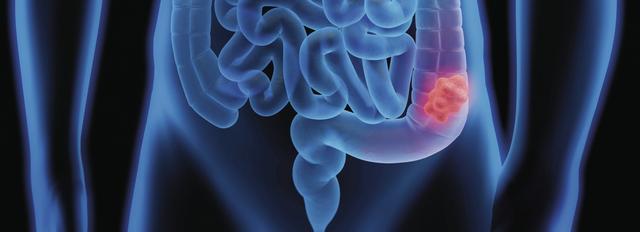

Aus einem Adenom kann sich Krebs entwickeln. Obwohl die meisten Adenome gutartig bleiben und keine weiteren Probleme verursachen, besteht ein gewisses Risiko, dass sie bösartig werden. Es ist wichtig, Adenome frühzeitig zu erkennen und zu behandeln, um das Risiko einer malignen Transformation zu minimieren. Daher werden regelmäßige Untersuchungen und Screenings empfohlen, insbesondere bei Personen mit einem erhöhten Risiko für Adenome oder Darmkrebs.

Ja, aus einem Adenom kann sich Krebs entwickeln. Obwohl ein Adenom anfangs gutartig ist, besteht das Risiko, dass sich einige dieser Wucherungen zu bösartigen Tumoren weiterentwickeln. Dies geschieht jedoch nicht in allen Fällen. Es ist wichtig, regelmäßige Untersuchungen durchzuführen und verdächtige Adenome frühzeitig zu erkennen und behandeln zu lassen.

Obwohl Adenome grundsätzlich als gutartig gelten, besteht dennoch das Risiko, dass sich aus einem Adenom Krebs entwickeln kann. Dieses Risiko variiert je nach Art des Adenoms und seinem Standort im Körper. Einige Arten von Adenomen haben ein höheres Potenzial zur Entartung als andere.

Obwohl Adenome grundsätzlich gutartig sind, besteht das Risiko, dass sie sich zu bösartigen Tumoren entwickeln können. Einige Adenome haben ein höheres Krebsrisiko als andere, abhängig von ihrer Lage und anderen Faktoren. Daher ist es wichtig, Adenome regelmäßig ärztlich kontrollieren zu lassen und gegebenenfalls zu behandeln, um das Risiko einer malignen Entartung zu minimieren.

Obwohl Adenome grundsätzlich als gutartig eingestuft werden, besteht bei ihnen das Risiko, dass sie sich zu bösartigen Tumoren entwickeln können. Es ist wichtig, Adenome regelmäßig ärztlich überwachen zu lassen und gegebenenfalls entsprechende Behandlungsmaßnahmen zu ergreifen, um das Risiko einer Krebsentwicklung zu minimieren.